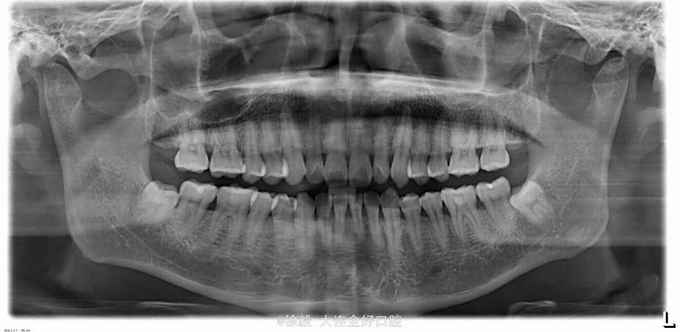

患者男性,40岁,体健。无遗传史。 患者前天就诊洗牙,治疗过程中发现上颌左上34颊侧,67舌侧明显有凸起,手触硬,无波动,无明显疼痛。右侧对应位置也有增生,但是凸起程度小。下颌前牙区舌侧也有黄豆大小凸起。 拍颌面ct和曲断检查,上颌左右45处有明显阴影区,右上45区在映像沙化过程中,骨密度透光变化明显。上颌左右67位置颊侧有致密骨映像,很像骨增生。 患者怀疑有没有恶性倾向,希望会诊一下。